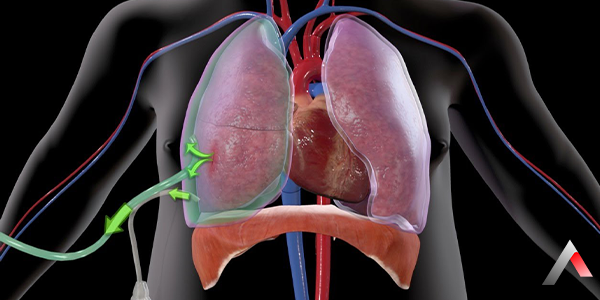

Akciğerlerimiz, göğüs boşluğunda yer alan ve solunum fonksiyonunu gerçekleştiren hayati organlardır. Akciğerleri çevreleyen iki zar tabakası bulunur: visseral plevra (akciğere yapışık olan zar) ve parietal plevra (göğüs duvarına yapışık olan zar). Bu iki zar tabakası arasında plevra boşluğu adı verilen ince bir sıvı tabakası bulunur.

Pnömotoraks, çeşitli nedenlerle plevra boşluğuna hava girmesi ve akciğer üzerinde baskı oluşturarak çökmesine neden olması durumudur. Bu durum, akciğerin solunum fonksiyonunu yerine getirmesini engeller ve ciddi sağlık sorunlarına yol açabilir.